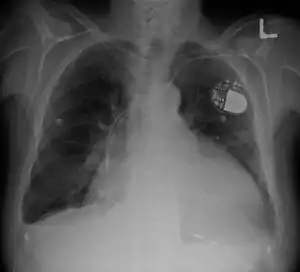

| Cardiomegaly on chest X-ray and a pacemaker | |

در پرتونگاری قفسه سینه، قلب بزرگشده را میبینیم که بیشاز پنجاهدرصد عرض قفسه سینه را پوشاندهاست. در الکتروکاردیوگرافی معمولاً انحراف محور قلب به چپ وجوددارد. اغلب بیماران اتساع بطنی یا هیپرتروفی بطنی یا هر دو را دارند.